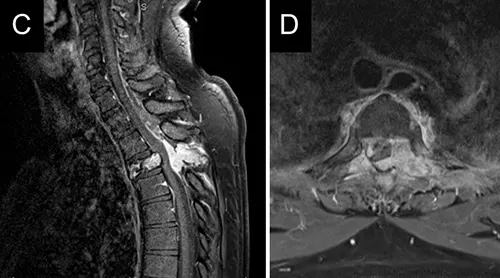

- Direct Invasion/Destruction: Primary bone tumors (like osteosarcoma) or metastatic tumors directly destroy bone tissue [3].

This accelerated bone resorption is a key mechanism leading to complications like pathological fractures (fractures occurring with minimal or no trauma due to weakened bone) and pain [2, 3]. Vertebral bodies are common sites for metastases and myeloma, and pathological compression fractures here can cause spinal cord or nerve root compression, representing neurological emergencies [3].

| Osteomyelitis | Focal bone destruction (lysis), periosteal reaction, sequestrum/involucrum (chronic). Often localized pain, swelling, fever. | Elevated WBC, ESR/CRP. Blood/bone cultures positive. MRI most sensitive early. X-ray changes lag. Bone scan positive. |